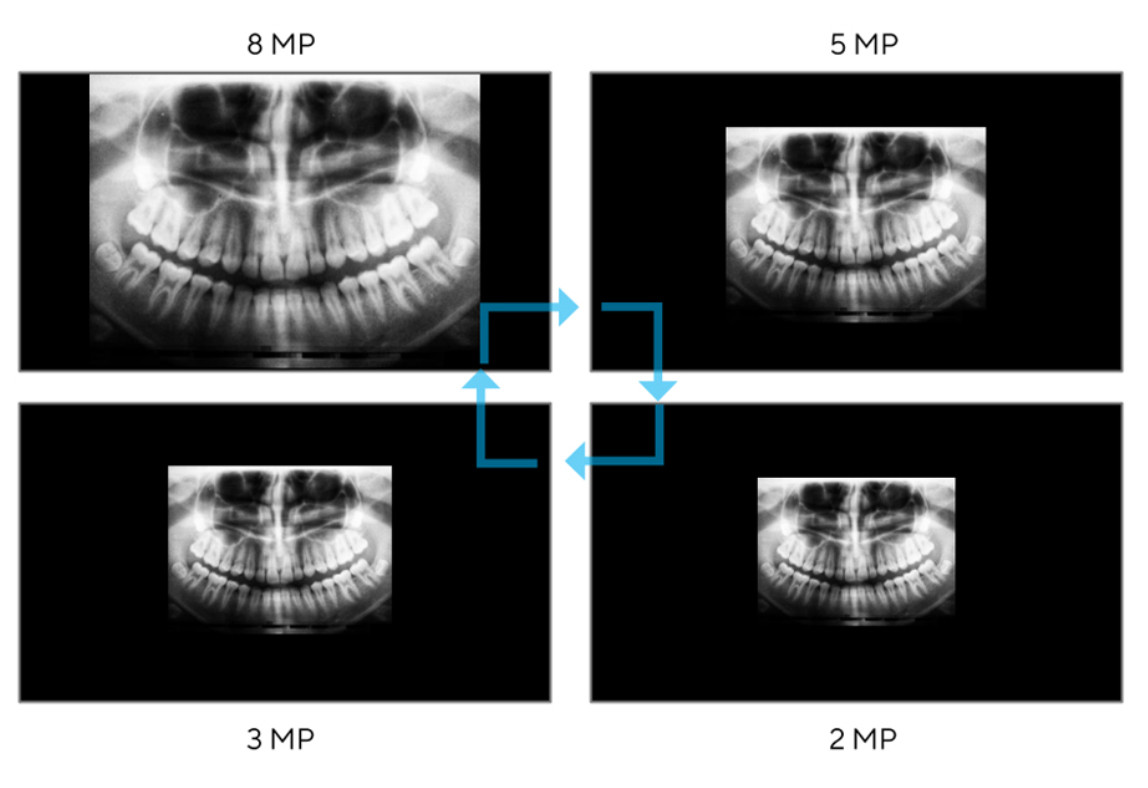

- 31,5 inç 8MP (3840 x 2160) saf RGB OLED gerçek 10-bit panel

- 31,5 inç 8MP (3840 x 2160) saf RGB OLED gerçek 10-bit panel